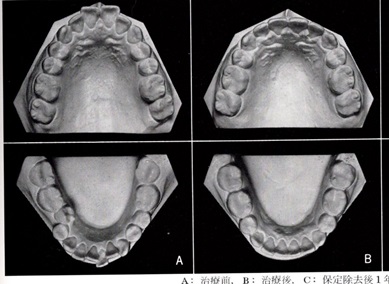

前回の写真を説明していきたいと思います。

Aは抜歯矯正治療前、Bは抜歯矯正治療後です。

AからBの移行時に第1小臼歯を上下4本抜いています。

そのために、上下顎の歯列弓が短縮されています。

特に下顎は舌の収納場所であるため、下顎の歯列弓が縮小すると舌が奥に引き込まれて下の右の図にあるように、無呼吸を起こしやすくなる形態を作ってしまいます。

左:正常の舌の位置 右:無呼吸時の舌の位置

歯を4本抜く事が歯列にどの様な影響を与えるのか図によって示していきたいと思います。

A:治療前 B:治療後

次回はこの図を使って説明していきたいと思います。